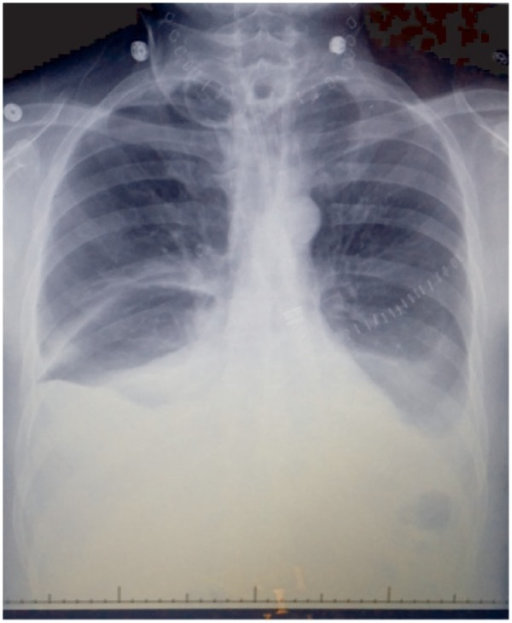

작은 유미흉은 증상이 없을 수 있으며, 다른 이유로 시행한 단순 가슴 방사선 사진(흉부 엑스레이)에서 우연히 발견될 수 있다. 큰 유미흉은 폐에 들어찬 체액이 폐의 팽창을 방해하여 숨이 차거나 가슴에 압박감을 유발할 수 있지만, 유미가 천천히 축적되면 폐가 압력에 적응할 시간이 있었기 때문에 증상이 나타나지 않을 수 있다. 유미 자체는 염증을 일으키지 않기 때문에 발열이나 흉통은 일반적으로 유미흉과 관련이 없다.[21]

가슴 엑스레이(CXR)나 초음파 영상으로 유미흉을 발견할 수 있다. 엑스레이상에서 유미흉은 갈비가로막각과 심장가로막각을 가리는 조밀하고 균일한 영역으로 나타나며, 초음파 영상에서는 격벽(septation)이나 소방의 형성(loculation)이 없는 등밀도(isodense) 영역으로 나타난다. 그러나 보통의 가슴 엑스레이나 초음파 검사로는 유미흉을 다른 유형의 흉수와 구별할 수 없다.[18]